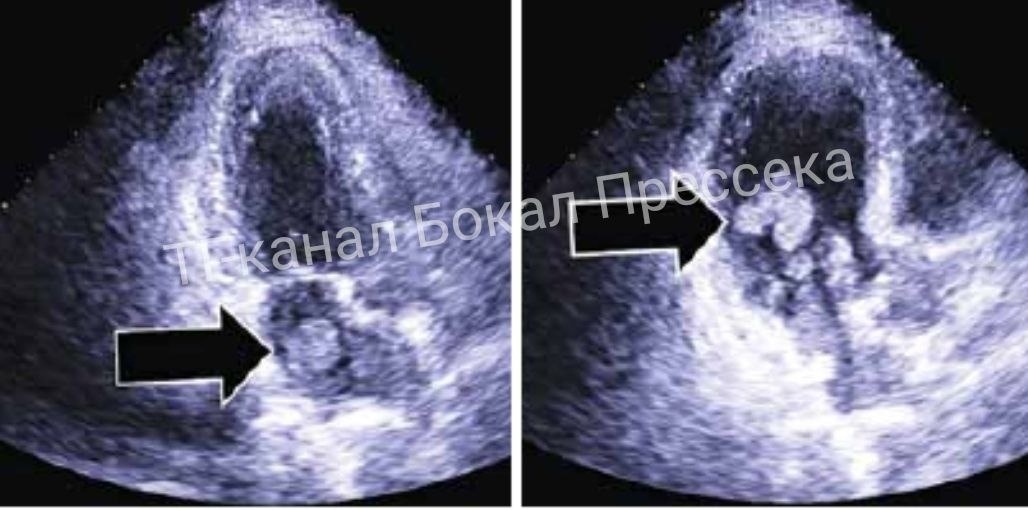

Миксому (редкая доброкачественная опухоль сердца, частицы рыхлого новообразования могут попадать в кровоток и провоцировать ишемический инсульт мозга) выявили на УЗИ сердца.